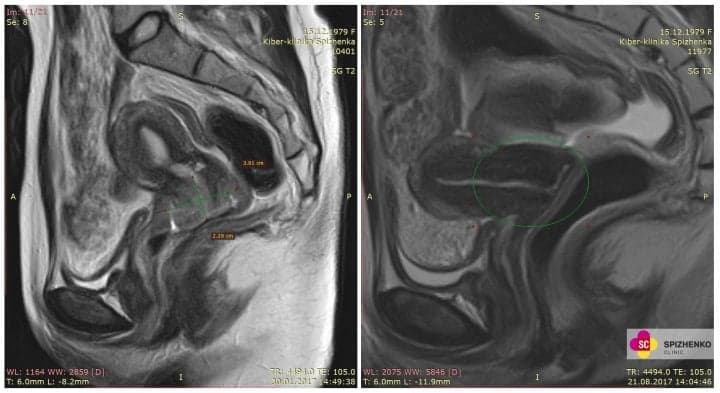

План променевої терапії, на якому висока дози підводиться в заданий обсяг, уражений пухлиною

План радіохірургічного лікування на КіберНожі — зона, позначена червоним кольором, отримала необхідну високу дозу іонізуючого випромінювання